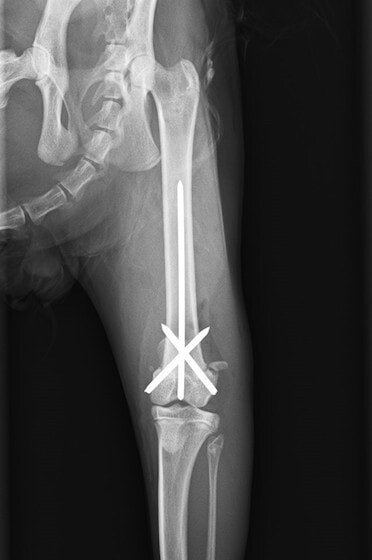

症例3:キルシュナーワイヤーのピンニングによる整復

ペルシャ猫 11ヶ月齢 雄

他院にて左大腿骨遠位の成長板骨折(salter-harrisⅠ型)が認められており、治療相談を目的として来院。当院にて、キルシュナーワイヤーを用いたピンニングにより骨折部位の整復を行いました。術後の経過は良好で、現在も経過観察中です。

術後レントゲン

Arthrex社のターゲティングデバイスを用いてピンニングの位置を調整することで、確実な固定を行っています。当院ではこの手術器具以外にも、人の手術にも使用される様々な器具を導入し、手術精度を高め、また医療メーカーと新しい器具の開発、試作にも取り組んでおります。